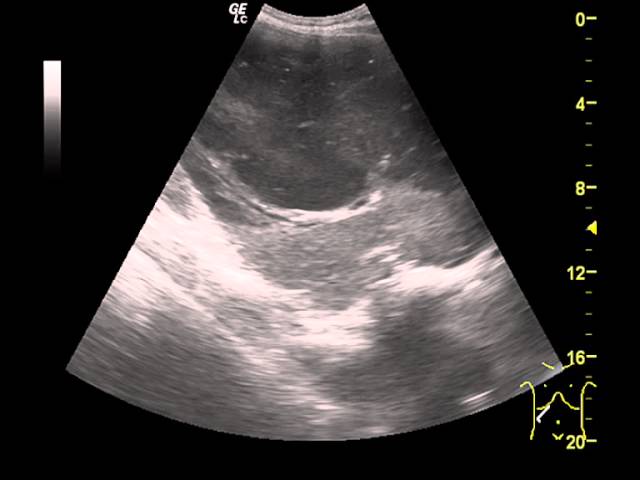

Врачи отмечают, что на УЗИ печени можно выявить различные образования, которые могут быть как доброкачественными, так и злокачественными. К наиболее распространённым доброкачественным образованиям относятся гемангиомы и аденомы. Гемангиомы выглядят как гиперэхогенные образования с четкими границами, тогда как аденомы могут иметь более неоднородную структуру. Злокачественные опухоли, такие как гепатоцеллюлярная карцинома, часто проявляются как гипоэхогенные участки с нечеткими контурами и могут сопровождаться изменениями в структуре печени. Врачи подчеркивают важность комплексного подхода к диагностике, включая анализы и дополнительные методы визуализации, чтобы точно определить природу образования и назначить соответствующее лечение.

В зависимости от характера клеток и структуры образования ультразвуковые волны отражаются с разной скоростью. Поэтому изображение на экране компьютера будет светлым или темным. Это свойство называется эхогенностью, а образования — гипоэхогенными, анэхогенными или гиперэхогенными.

Изоэхогенные участки — соответствующие нормальной печеночной структуре. Гипоэхогенность возникает, когда почти все волны поглощаются очагом. Гиперэхогенность соответствует более сильному отражению звука. Анэхогенные участки поглощают звук полностью, он от них не отражается.

- Киста — гипоэхогенное полостное образование с плотной стенкой. Внутри содержится жидкость, различные включения. Киста формируется из желчных протоков или представляет собой скопление паразитов, покрытых капсулой. Для паразитарных кист характерна множественность — в одной левой доле печени их может быть до 5 штук.

- Гемангиома. Сосудистая опухоль, состоит из множества расширенных капилляров. Этим объясняется, как выглядит гемангиома печени на УЗИ — очаг с неровными краями, неоднородной структурой.

- Абсцесс. Гнойное воспаление, отграниченное капсулой. Имеет округлую форму, уровень жидкости внутри, гипоэхогенно.

- Гематома — скопление излившейся крови, на УЗИ представлено гипоэхогенным участком округлой формы.

Злокачественно преображенные клетки имеют большую плотность, поэтому обладают повышенной эхогенностью относительно здоровой части печени. Очаги с неровными контурами, от нескольких миллиметров до десятков сантиметров в диаметре.